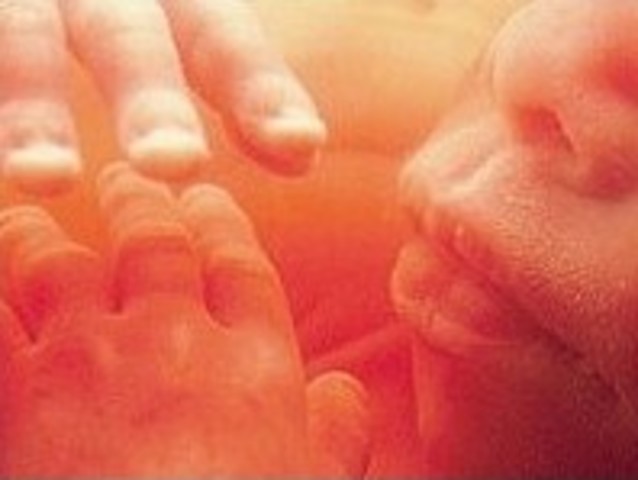

Fingers and toes completely seperated, tastebuds develop, baby can stick out tongue and swallow. Most of the body is sensitive to touch. (If gender is male, testicles start producing testosterone.)

• Week 12

Week 12

Fetus is 2.5 inches, starts moving spontaneously. Face begins to look like a baby face, pancreas produces insulin, the fingernails and toenails appear, baby can suck thumb and get hiccups baby can feel pain.